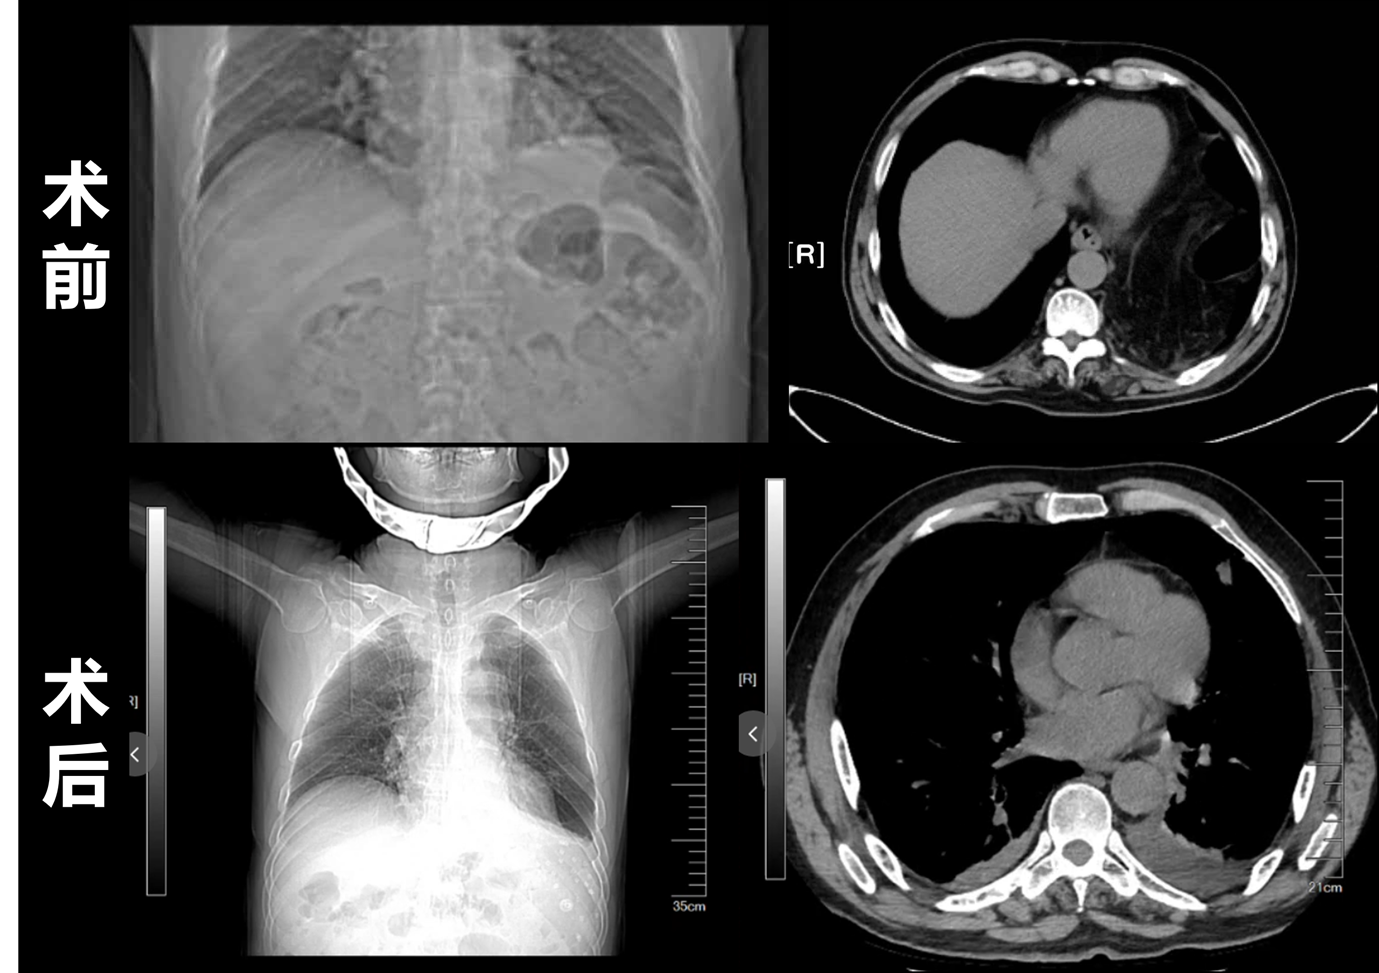

▼膈疝的腹腔镜个体化手术修补方式操作图片

患者一:食管癌根治术后8年余,10天前无明显诱因出现停止排气、排便,于当地医院行CT检查提示左侧膈疝并小肠梗阻。患者辗转多家医院后来院急诊就诊。疝与腹壁外科李波主任详细研判病情后,将患者转入科室行腹腔镜探查+膈疝修补术,术中见大量小肠经膈肌缺损处疝入左侧胸腔并发生嵌顿。因手术处置及时,患者术后恢复顺利,现已康复出院。

患者二:患者10年前有过车祸伤史,1天前突发腹痛,伴停止排气排便,当地医院CT检查提示左侧膈疝合并结肠梗阻,辗转转入我院急诊。李波主任详细了解病情,考虑患者为慢性创伤性膈疝伴结肠嵌顿,为防止结肠嵌顿坏死,立即启动急诊手术,行腹腔镜探查+膈疝修补术。术中可见横结肠、结肠脾曲及大量大网膜经左侧膈肌缺损疝入胸腔。得益于手术干预及时,有效避免了肠管坏死风险,患者术后恢复顺利。